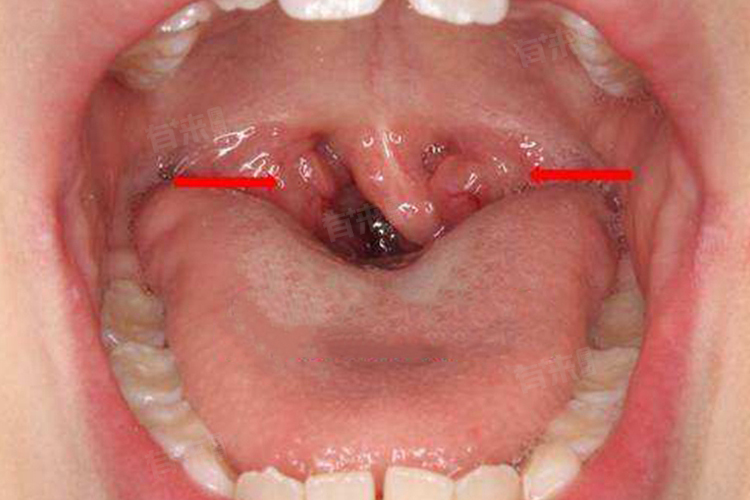

- 但也有一些情况下扁桃体肥大难以自行恢复,可能需要手术干预,如扁桃体肥大严重,导致气道狭窄、呼吸困难、睡眠呼吸暂停等症状,或者反复发作的扁桃体炎,影响孩子的日常生活和学习,以及扁桃体肥大伴随有其他严重并发症,在这些情况下,手术切除扁桃体成为了有效的治疗手段,能够显著改善孩子的呼吸状况和整体健康,促进疾病恢复。